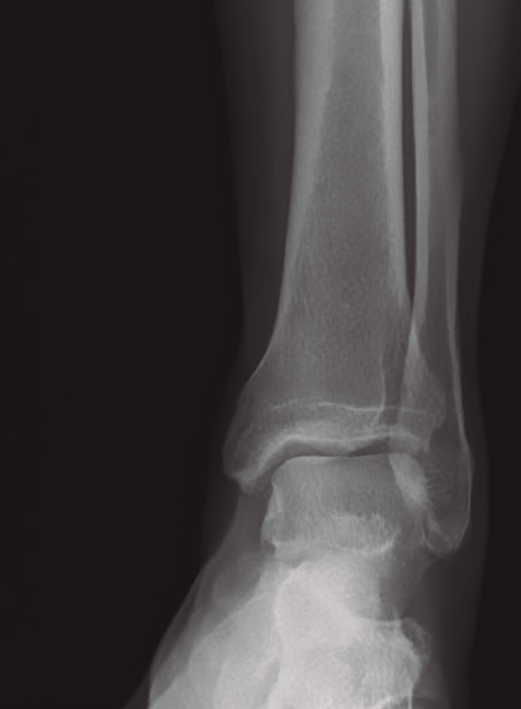

Figura 2. Radiografía preoperatoria. Se aprecia la exóstosis a nivel submaleolar peroneal.

Se realizan los estudios complementarios mediante radiografías, en las que se observa una lesión ósea en la cara lateral del calcáneo con bordes irregulares (Figura 2). La resonancia magnética nuclear informa de “hipertrofia del tubérculo lateral del calcáneo que conlleva severa afectación de los tendones peroneos apreciando signos de tenosinovitis y afectación mayor del tendón peroneo lateral largo con rotura parcial del mismo” (Figuras 3A y 3B). La tomografía computarizada muestra una “exóstosis en cara externa de calcáneo de 12 × 9 × 8 mm” (Figuras 4A y 4B).